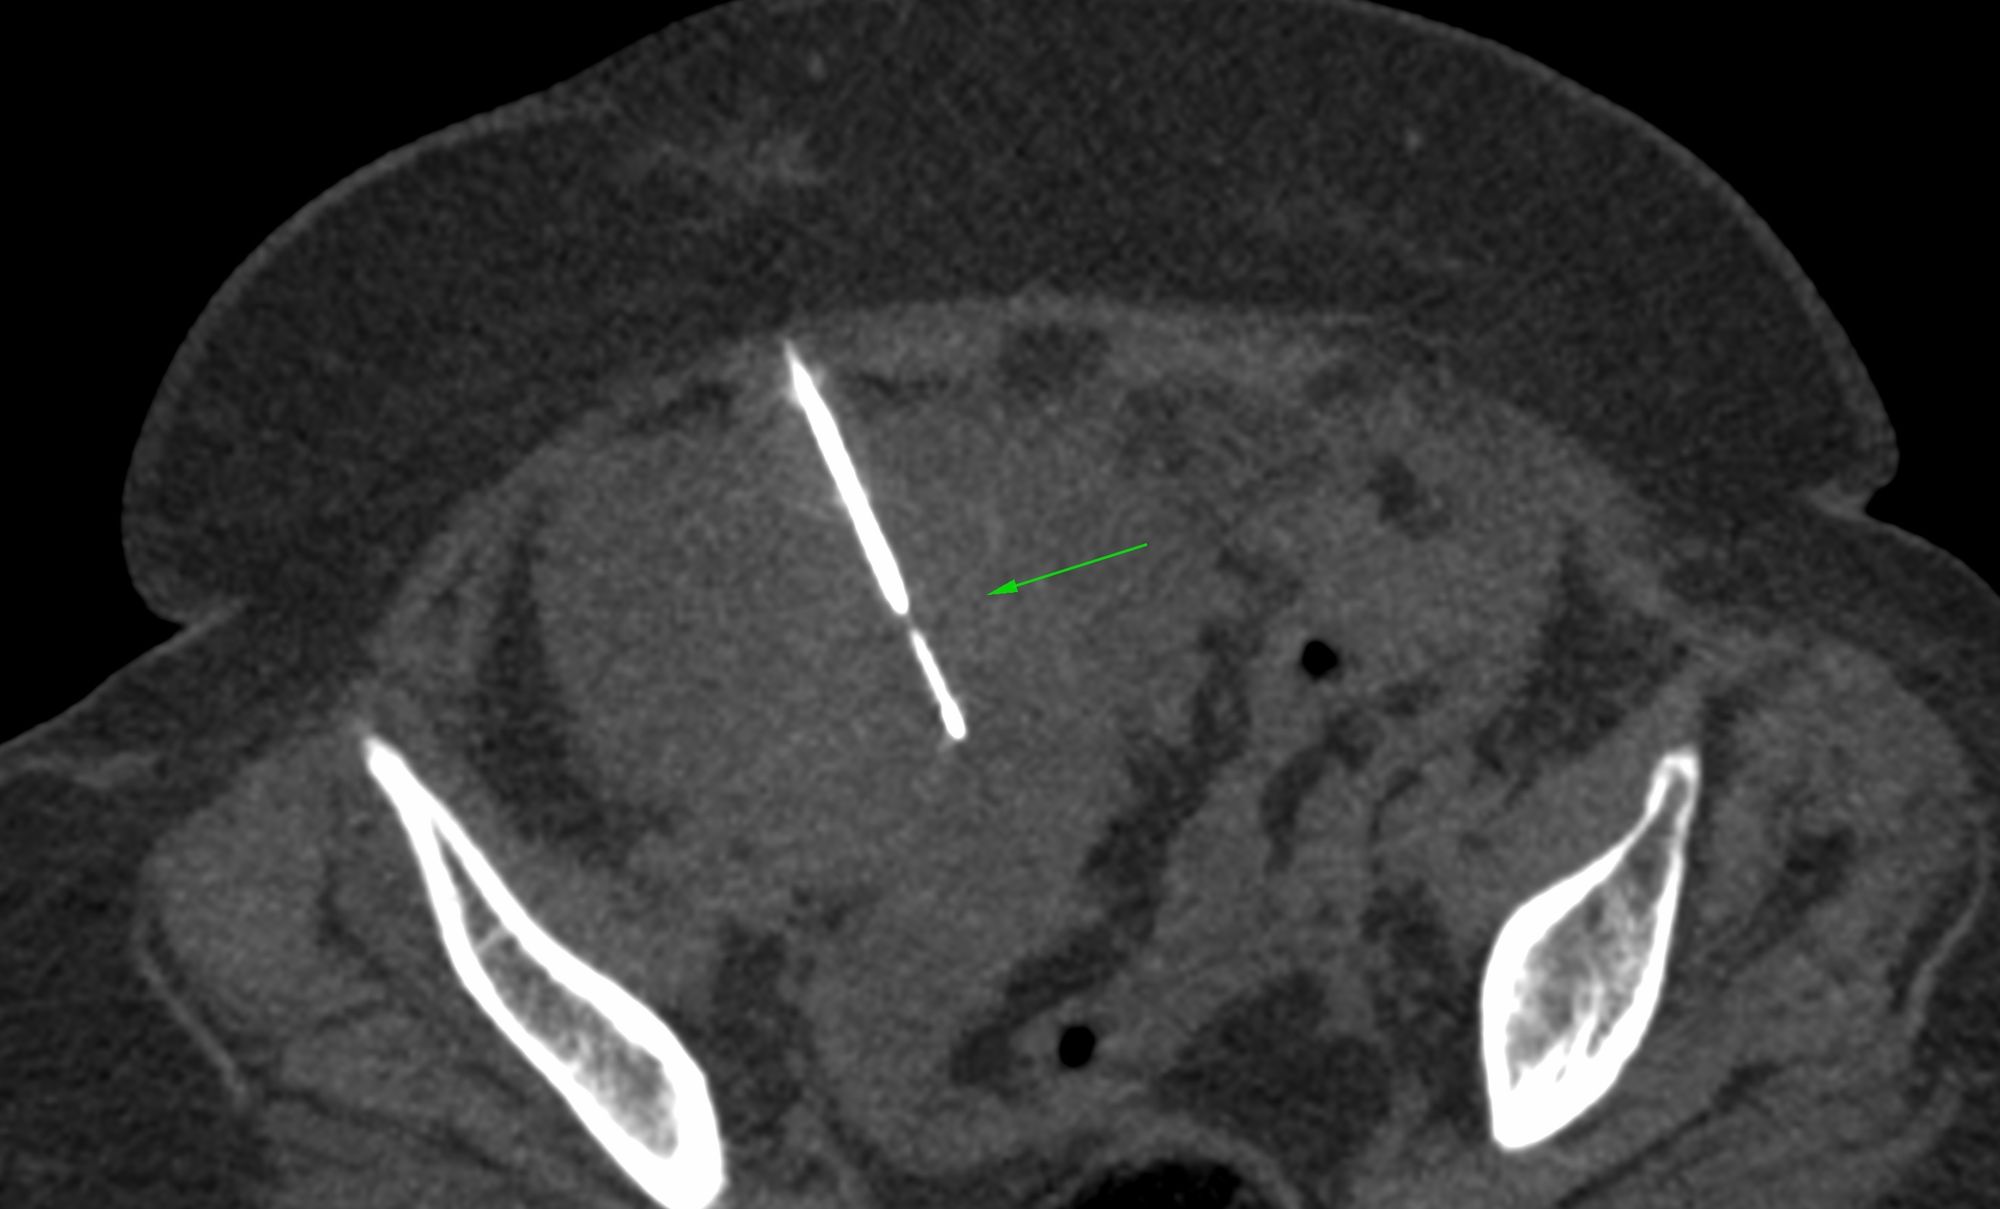

Case 48: Ovarian Mass Biopsy – Approach – Anterior or Posterior?

Bhavin Jankharia - 12 July 2021